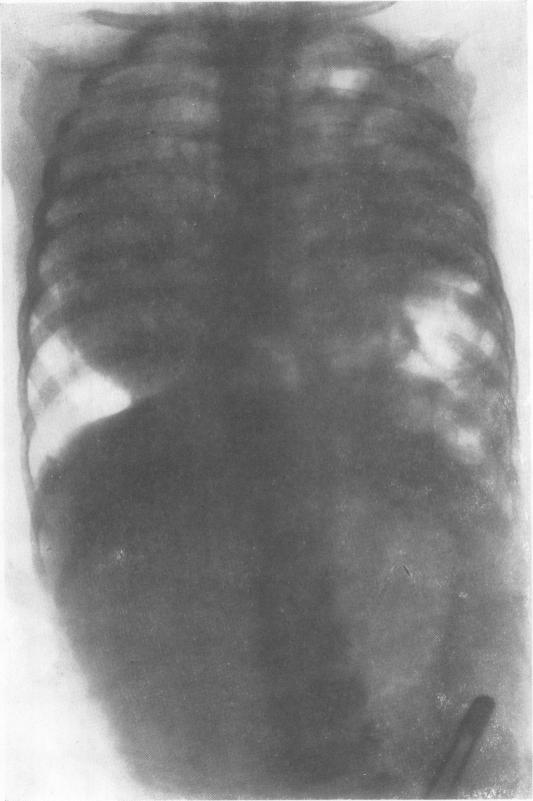

Fifty-seven cases of diaphragmatic hernia and eventration.

Thorax. 1950 Dec;5(4):343-61. doi: 10.1136/thx.5.4.343.